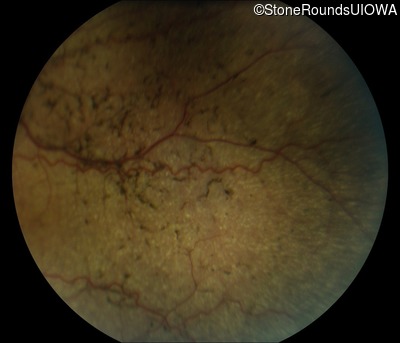

Fundus Photography - Right - 10/600

Exemplar

Fundus Photography - Left - 20/100 -2